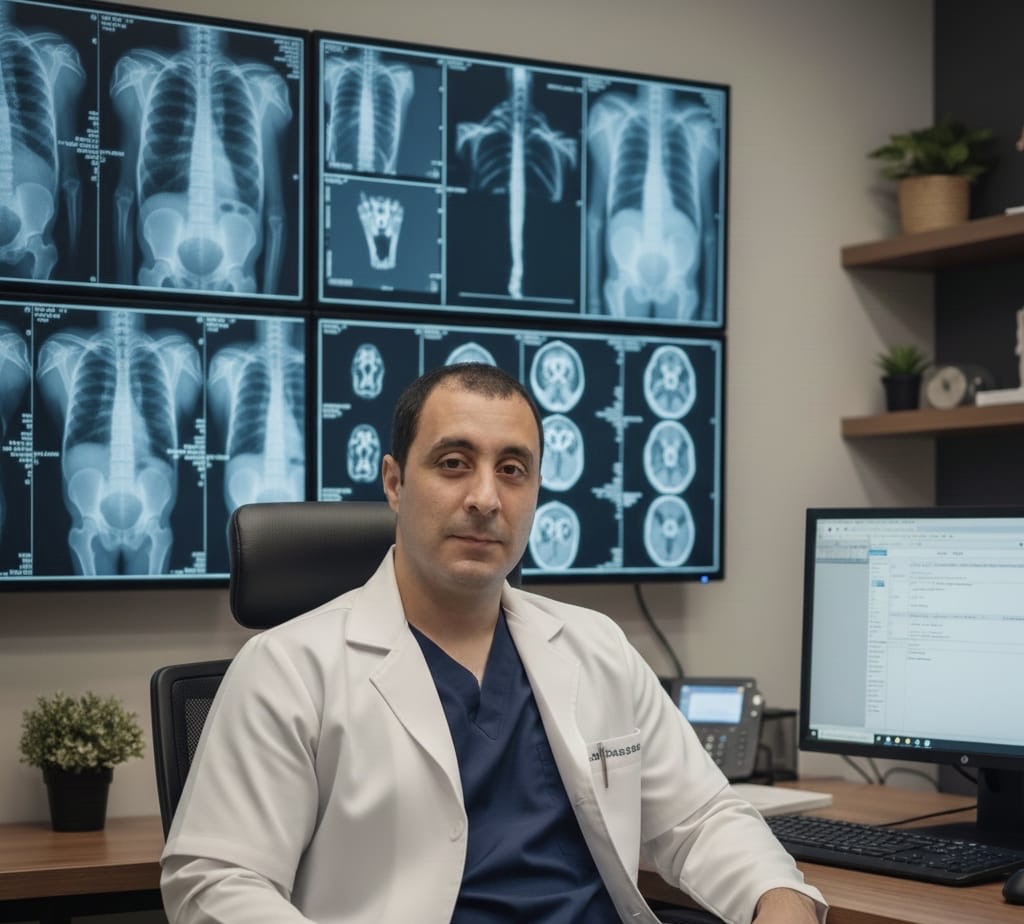

Joseph jackaman Juha

Médico Especialista en Radiología

Dr Joseph jackaman Juha

Médico Especialista en Radiología